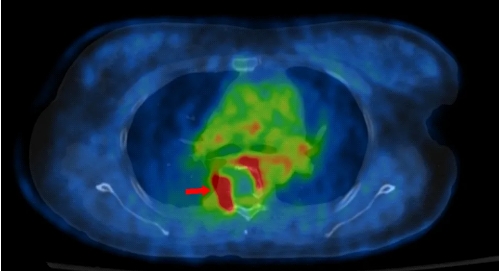

PET和CT融合后的图像

箭头所示红色区域为骨转移高代谢区